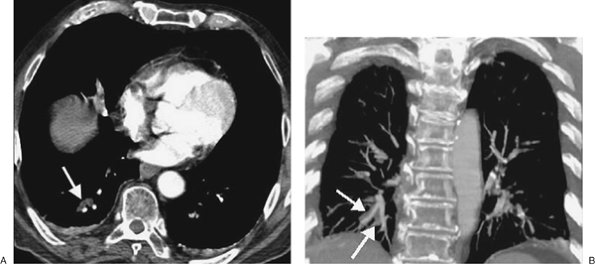

FIGURE 17-3. Acute PE. A: CTPA of a 77-year-old man with shortness of breath shows an intraluminal filling defect, surrounded by a rim of contrast, within the right lower lobe segmental pulmonary arteries (arrow). B: Coronal CTPA shows decreased caliber of arteries in the right lung compared with the left and filling defect within right lower lobe vessels. C: Catheter-based pulmonary angiogram confirms clot within right lower lobe vessels (arrows).

FIGURE 17-4. Acute PE. A: CTPA of a 77-year-old woman with a gastrointestinal bleed and DVT shows an intraluminal filling defect in a left lower lobe segmental pulmonary artery (arrow). B: CTPA at a more superior level shows intraluminal filling defects, surrounded by contrast material, in the right middle lobe and left lower lobe pulmonary arteries (arrows). C: CTPA at a level superior to (B) shows an intraluminal filling defect, surrounded by a thin rim of contrast material, in a right lower lobe segmental pulmonary artery (arrow).

FIGURE 17-5. Acute PE. A: CTPA of a 78-year-old woman shows an intraluminal filling defect surrounded by contrast material in the proximal right lower lobe pulmonary artery (arrow). B: Coronal CTPA shows that the intraluminal filling defect extends from the proximal right lower lobe pulmonary artery inferiorly to distal branches (arrows). C: CTPA with lung windowing shows oligemia and diminution of vessels on the right (Westermark sign).